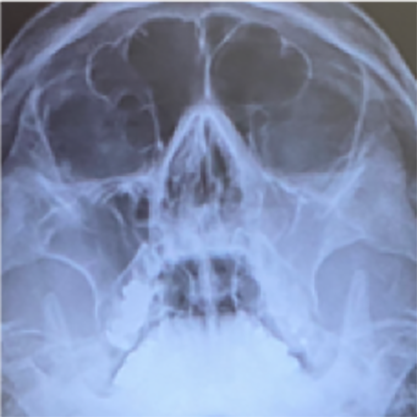

頭蓋内合併症(CT)

CTにて頭蓋内合併症が疑われる。